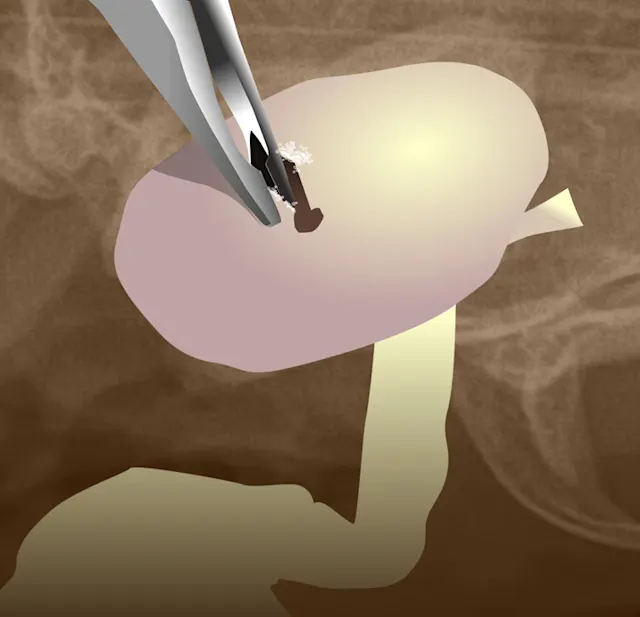

The polyp was incompletely removed, and the remaining portion cannot be removed with forceps via manual traction (Figure 4).

FIGURE 4 This nasopharyngeal polyp has a long thin stalk, which usually indicates that the root of the polyp has been retrieved.